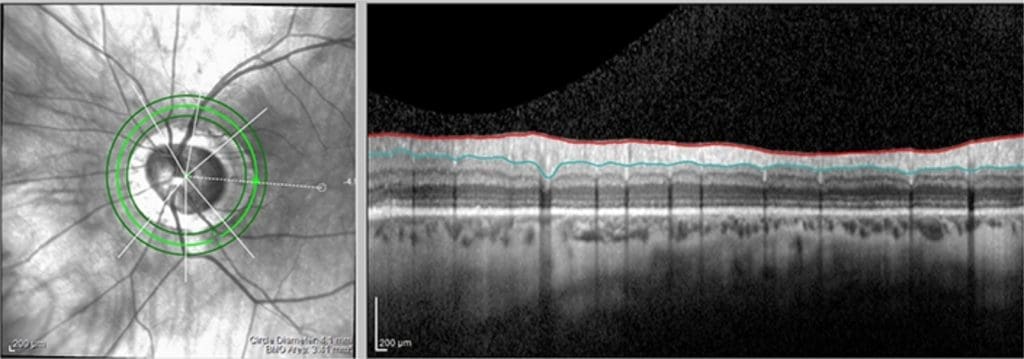

Das neuartige Gerät, das im Projekt FALCO entwickelt werden soll, wird auf der optischen Kohärenztomografie (OCT) basieren. Bei diesem bildgebenden Verfahren werden dreidimensionale Aufnahmen der Netzhaut des Auges in Mikrometerauflösung angefertigt, um Verformungen an der Oberflächenstruktur sichtbar zu machen. Sind welche zu sehen, liegt ein Glaukom vor. „Bei konventionellen klinischen Systemen dieser Art fährt ein Laserstrahl automatisiert über das Auge und misst es. Die beweglichen Teile, die hierfür notwendig sind, müssen sehr präzise und schnell arbeiten und sind daher sehr teuer“, so Oberheide.